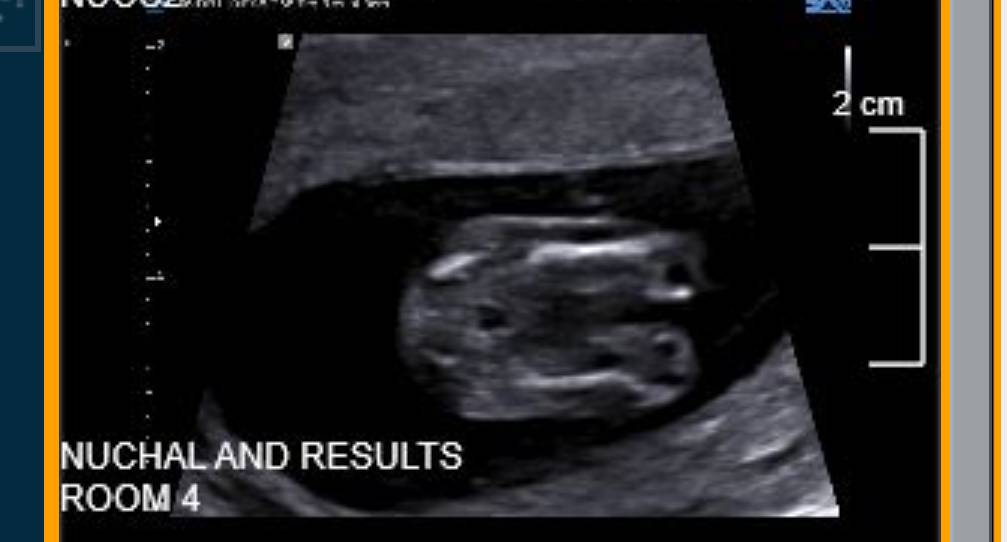

Thanks so much, I completely respect the sonographer for not speculating, am just so curious. Here is the only other shot that is vaguely sideways but I can't tell if it is showing the nub or not. Any thoughts greatly appreciated. Attachment 42109

Yeah, the upsidedown shots are no good unfortunately, plus the nub is not really clear in that one. I hope you get what you're wishing for!